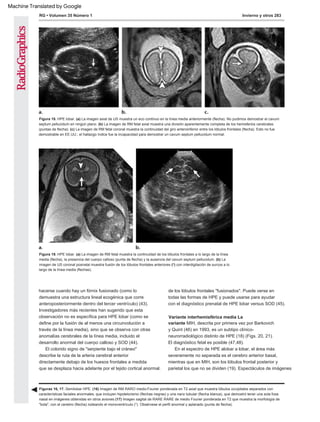

Figura 7. Alobar HPE. (a) La imagen de US axial oblicua obtenida a las 18 semanas muestra tálamos fusionados

(puntas de flecha) y un monoventrículo (*). (b) La ecografía axial oblicua obtenida a un nivel más alto muestra la

morfología en forma de copa de los hemisferios no hendidos (flechas) "ahuecando" el monoventrículo (*).

Figura 11. Alobar HPE. La imagen de RM fetal axial muestra un

único monoventrículo primitivo (*) rodeado de tejido cerebral

anormal. Esto se describe como el cerebro "en forma de bola".

Figura 8. Alobar HPE. La imagen de RM fetal coronal muestra un

monoventrículo (punta de flecha), hipotelorismo (flechas negras)

y una hendidura facial en la línea media (flecha blanca).

Aq = acueducto de Silvio, H = hipocampo, T = partes de tálamos

en forma de mancuerna (etiquetados por neuropatholo gist).

(Reimpreso, con autorización, de Amirsys.)

Figura 9. Alobar HPE. Imagen de RM fetal sagital que muestra un

gran “quiste dorsal” (puntas de flecha) y una morfología de “copa”

del cerebro (flecha). Obsérvese el perfil fetal normal en este caso.

Alobar HPE no siempre se asocia con facies dismórfica.

Figura 10. Alobar HPE. La vista de la autopsia fetal desde arriba

del cerebro muestra una morfología de "copa" del manto cerebral

sin división en hemisferios. El quiste dorsal desinflado se refleja

en la mitad de la bóveda del cráneo bivalvo.